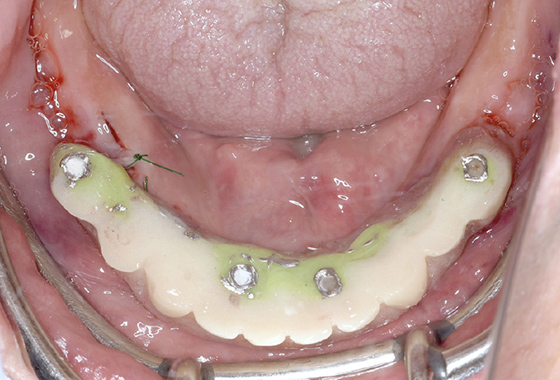

下の歯の抜歯後インプラント

手術当日に仮歯装着

• 手術当日に仮歯装着

最終補綴物装着

下顎の歯がしっかりと固定され、きちんと噛めるようになりました。

仮歯装着